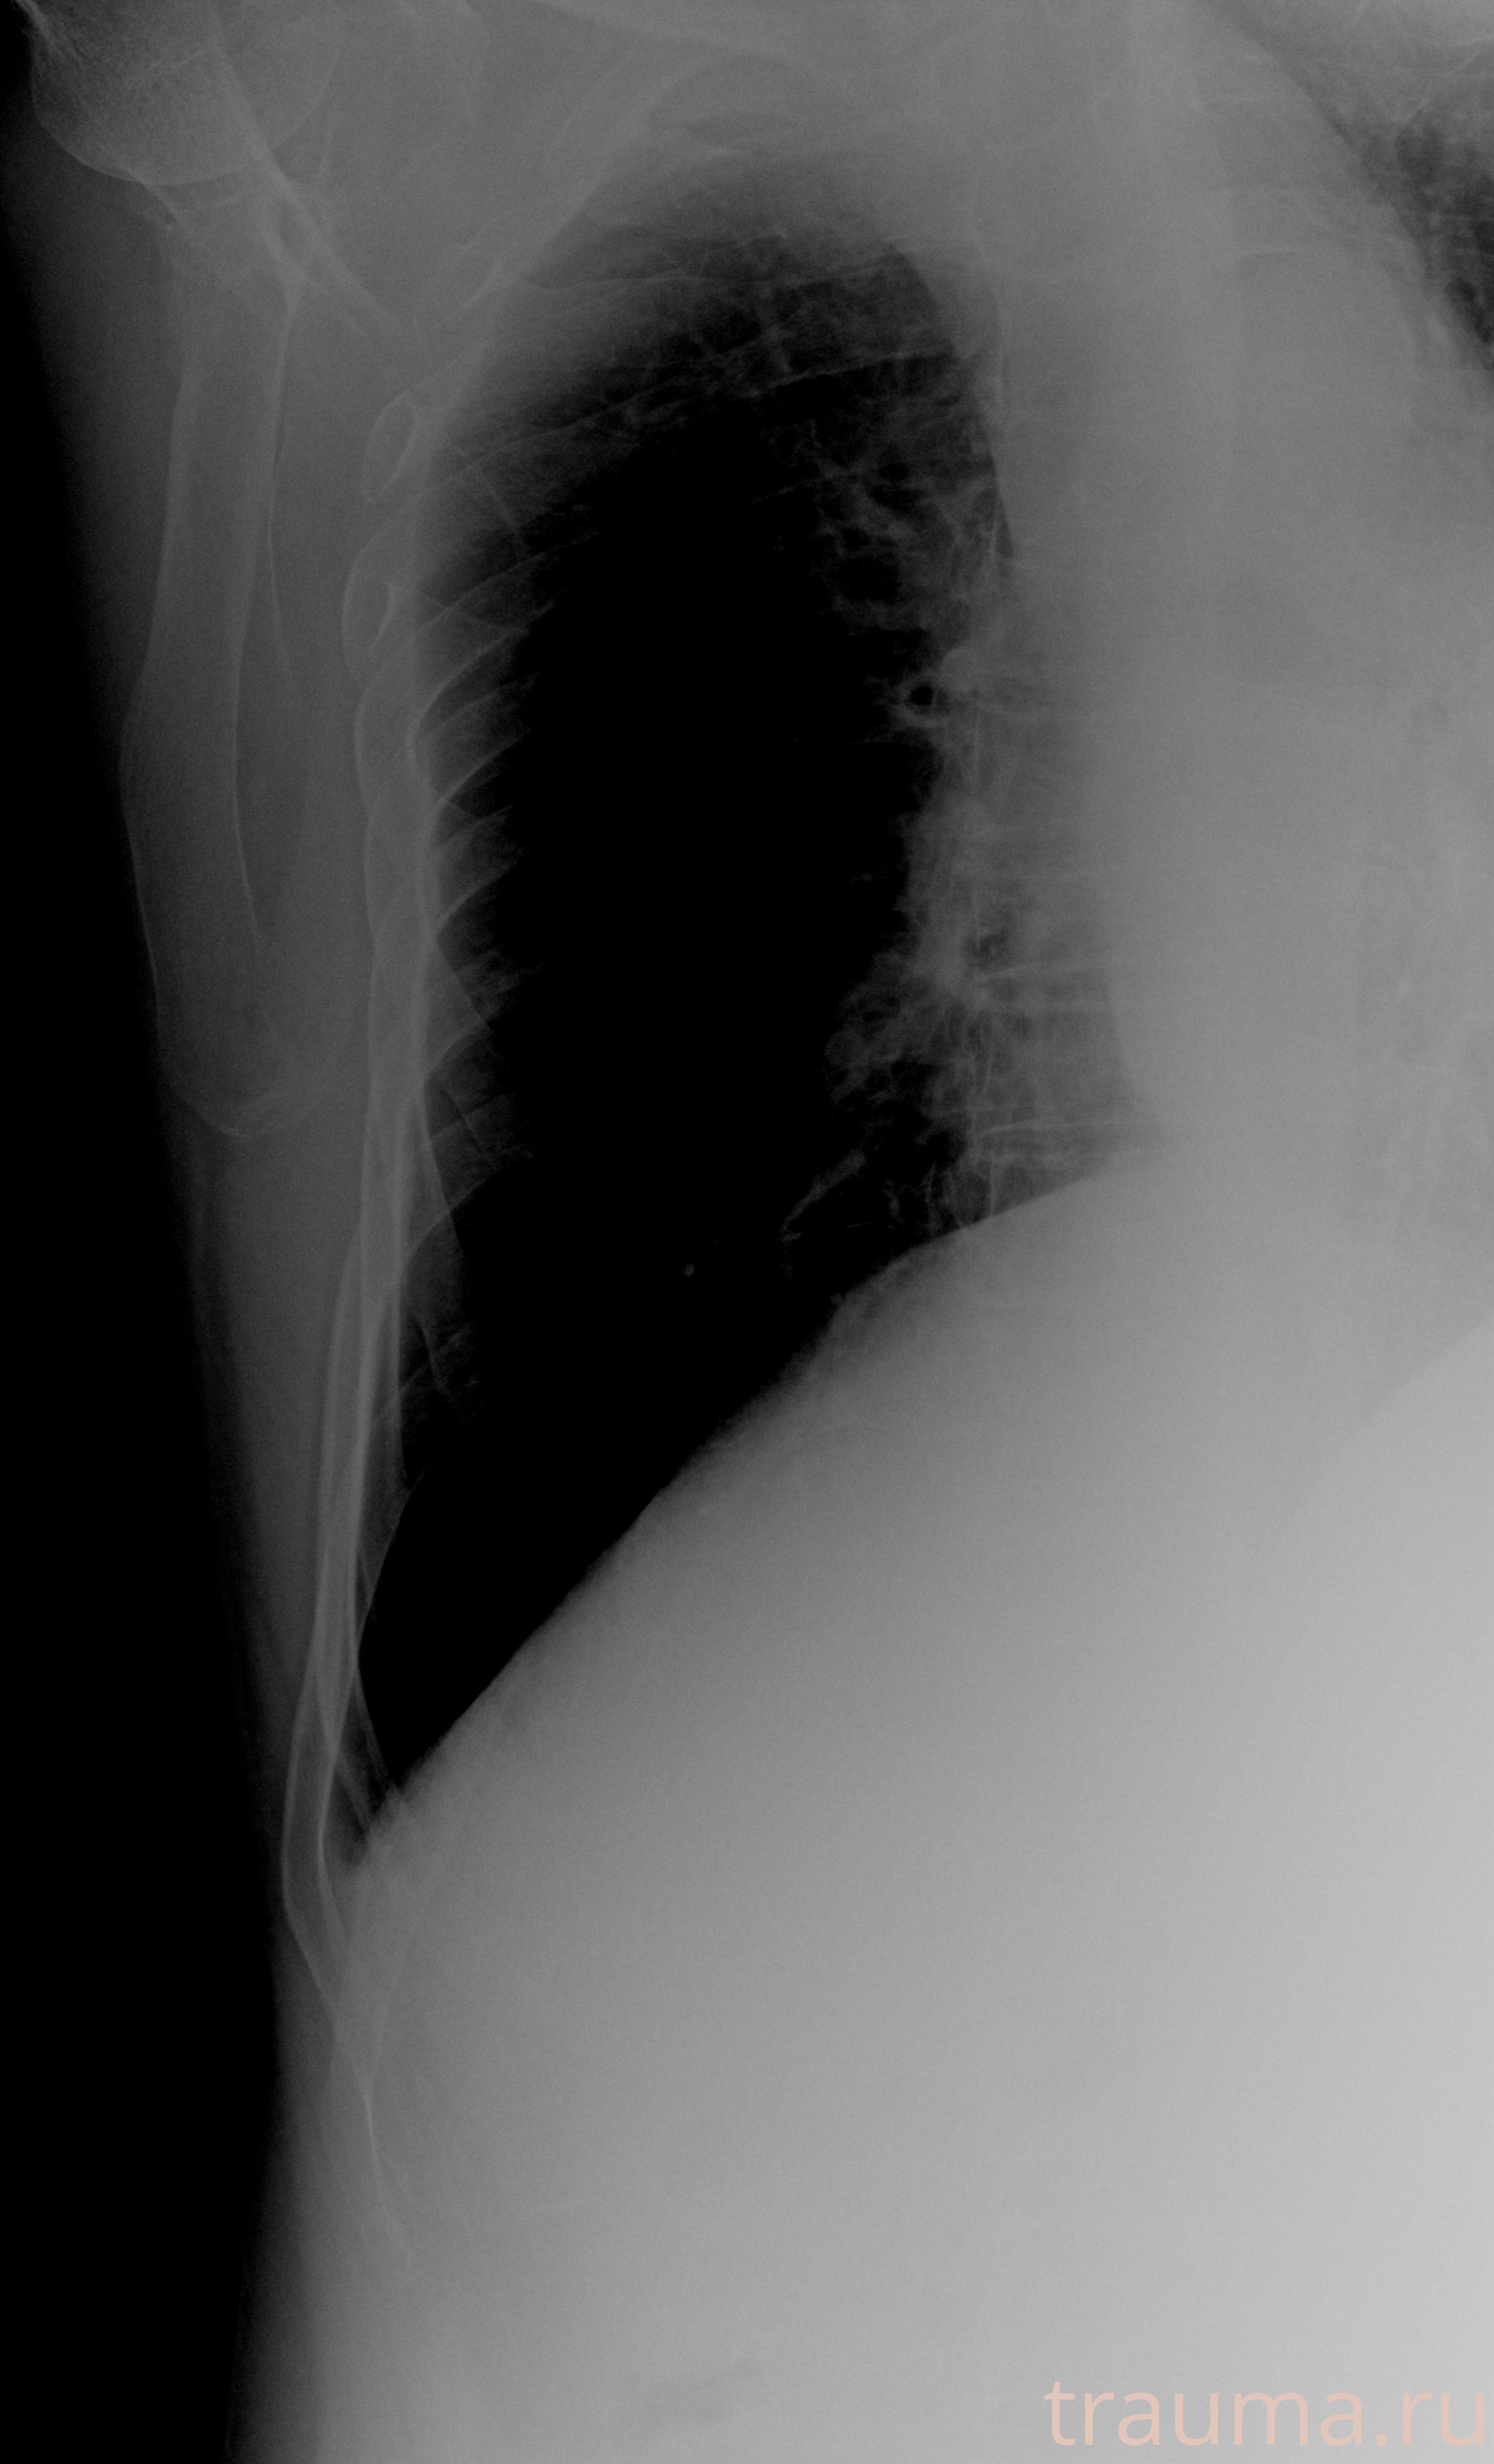

Рентгенограммы

Рентген на дому: по вашему адресу приезжает врач-рентгенолог, травматолог-ортопед с мобильным рентгеновским аппаратом, проводит диагностику травмы или заболевания, делает необходимые рентгенограммы, дает рекомендации по дальнейшему лечению. Получить качественные снимки в домашних условиях возможно благодаря уникальной методике, разработанной МосРентген Центром для института  Склифосовского

Яркость: 1   Контраст: 1   Инвертировать: 0 Увеличение: 1

Перетаскивайте мышь вверх/вниз для контраста, влево/право для яркости. Прокрутка колесом изменяет масштаб. Нажмите Сбросить для возврата к исходному изображению. При увеличении держите мышь в той области, которую хотите рассмотреть.